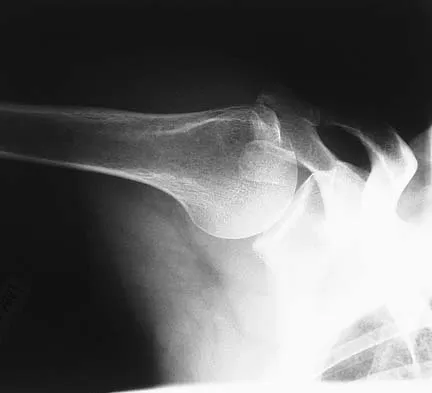

A 28-year-old professional dancer reports a 3-month history of progressive pain in the posterior aspect of the left ankle. Her symptoms are worse when she assumes the en pointe position. Examination reveals tenderness to palpation at the posterolateral aspect of the ankle posterior to the peroneal tendons which is made worse with passive plantar flexion. There is no nodularity, fluctuance, or tenderness of the Achilles tendon. The neurovascular examination is unremarkable. A lateral radiograph and MRI scan are shown in Figures 16a and 16b, respectively. Management should consist of

The imaging studies reveal findings typical of the os trigonum syndrome. This condition results from inflammation between the os trigonum and the adjacent talus. The symptoms of posterior ankle pain are exacerbated by plantar flexion, which stresses the fibrous union between these two bones. Definitive management of the high-level athlete involves excision of the os trigonum from a medial approach, although arthroscopic excision has also been described. The os trigonum is not an intra-articular structure; therefore, ankle arthroscopy is neither diagnostic nor therapeutic. Abramowitz Y, Wollstein R, Barzilay Y, et al: Outcome of resection of a symptomatic os trigonum. J Bone Joint Surg Am 2003;85:1051-1057. Mouhsine E, Crevoisier X, Leyvraz P, et al: Post-traumatic overload or acute syndrome of the os trigonum: A possible cause of posterior ankle impingement. Knee Surg Sports Traumatol Arthrosc 2004;12:250-253.